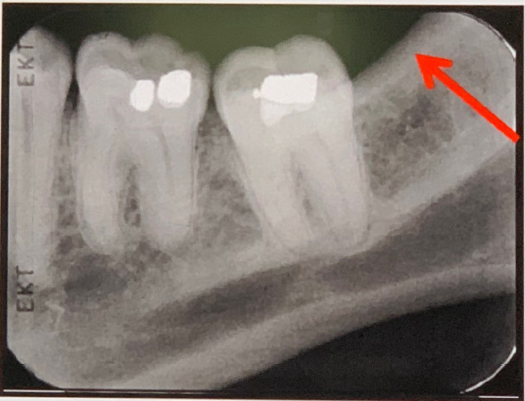

95. What is showing by red arrow?

External Oblique Ridge a continuation of the anterior border of the mandibular ramus. It follows an anteroinferior course lateral to the alveolar process.